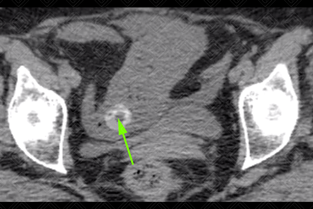

Texto alternativo para a imagem Figura 2. Créditos: Dra. Elazir Mota - Rio de Janeiro/RJ

Descrição das imagens: Tomografia computadorizada de abdome sem contraste. Vesícula biliar apresentando cálculo no seu interior (seta vermelha). Observe que não há um plano de clivagem nítido entre a vesícula biliar e o bordo duodenal (seta amarela), inclusive com uma duvidosa solução de continuidade entre eles. Na porção mais inferior do abdome, vemos distensão líquida gasosa, com caracterização de um ponto de transição de calibre no íleo distal por cálculo biliar (seta verde), confirmando a presença de íleo biliar.

• Tomografia computadorizada do abdome: T rata-se d o exame de escolha diante desta suspeita por permitir boa caracterização do cálculo no interior da alça intestinal. Apresenta uma acurácia, sensibilidade e especificidade elevadas. A tríade de Rigler inclui três achados de imagem: aerobilia, obstrução do intestino delgado e cálculo de via biliar ectópico (figura 2);